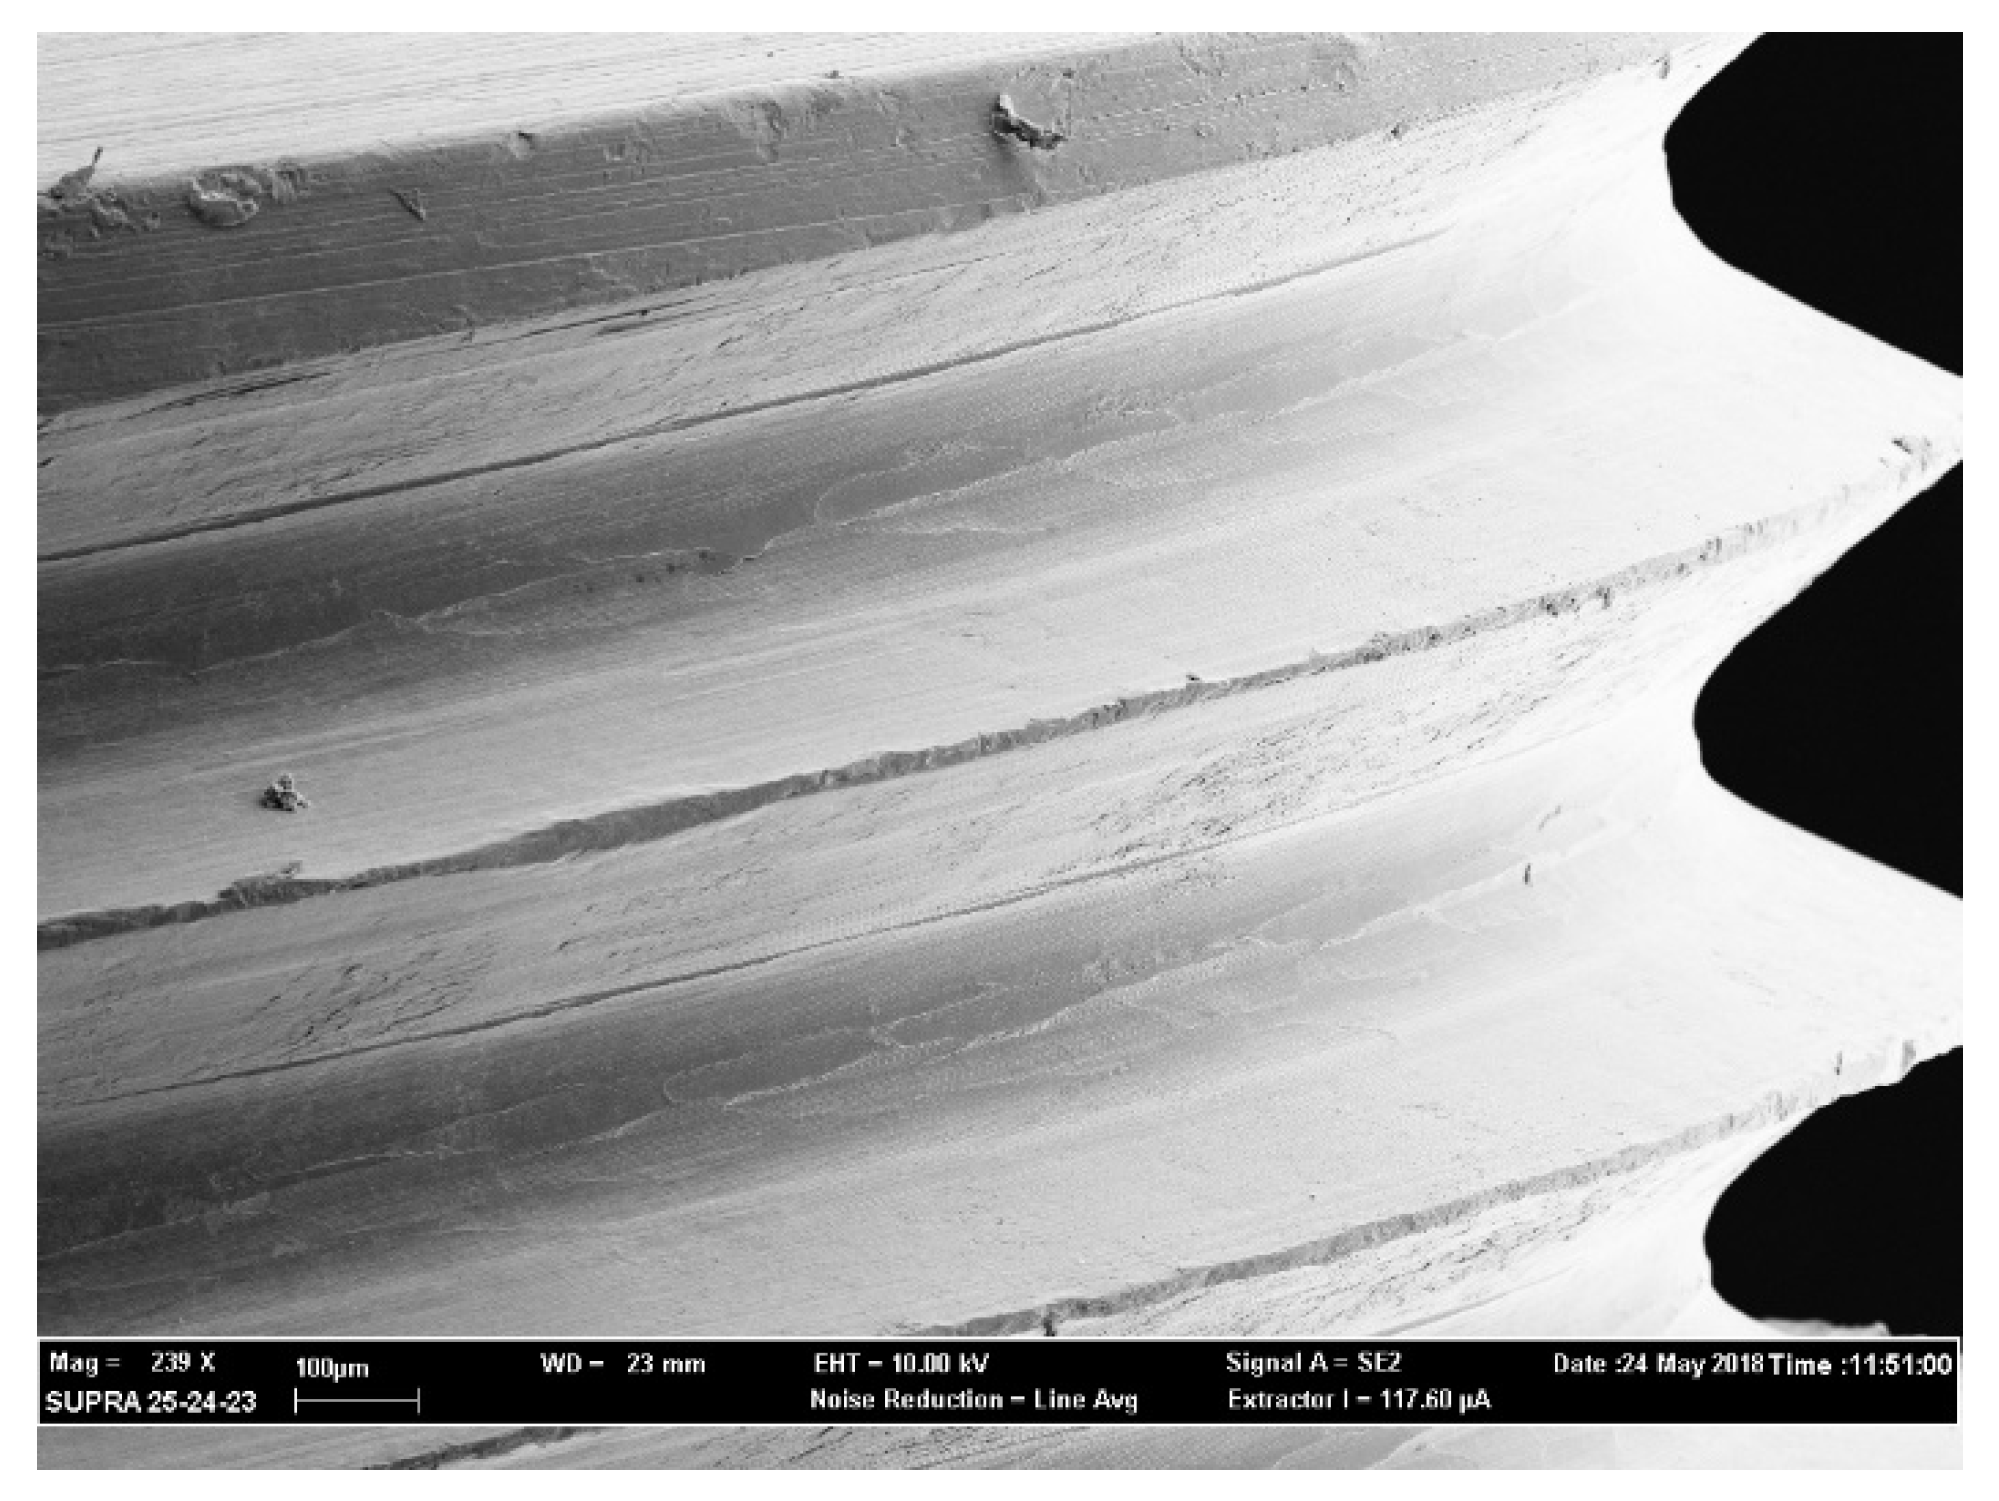

4.4. SEM Observation